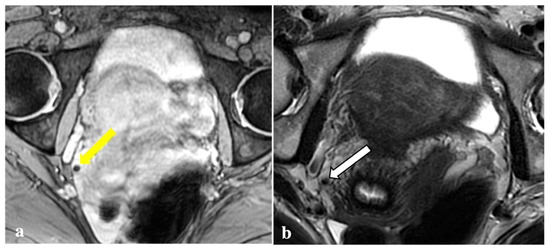

3.2. MRI Findings